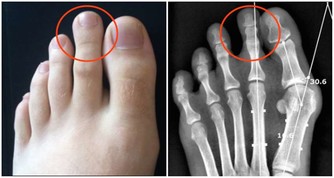

重點在姆趾的「環軸關節」(頭頸接合處)反射區,確實按壓這裡,

就能解開上身痠痛的結,立馬感覺無比舒暢!

「環軸關節」在哪裡?有憂鬱傾向的人這會痛。 「環軸關節」是指頭部和頸部接合處的關節,

位在第一頸椎和第二頸椎之間;其反射區在腳姆趾趾腹上方1/3的橫切線。

對應部位1/環軸關節(1點按壓)

刺激姆趾腹前段「環軸關節」的反射區,

棉花棒垂直握拿,朝趾尖方嚮往上按壓;慢慢地往橫向點按。